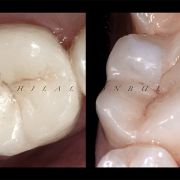

Based on evidence, all posterior teeth should be restored with cuspal coverage after root canal treatment. However, most of these teeth are badly destructed due to caries or large existent restoration. The key of success is to preserve the remaining tooth structure and restore the tooth conservatively. Dr khalid Merdad and I worked simultaneously to accomplish this task.